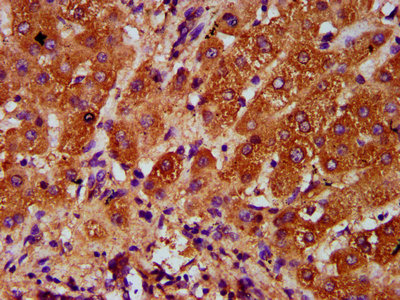

IHC image of CSB-PA883373LA01HU diluted at 1:400 and staining in paraffin-embedded human liver cancer performed on a Leica BondTM system. After dewaxing and hydration, antigen retrieval was mediated by high pressure in a citrate buffer (pH 6.0). Section was blocked with 10% normal goat serum 30min at RT. Then primary antibody (1% BSA) was incubated at 4°C overnight. The primary is detected by a biotinylated secondary antibody and visualized using an HRP conjugated SP system.